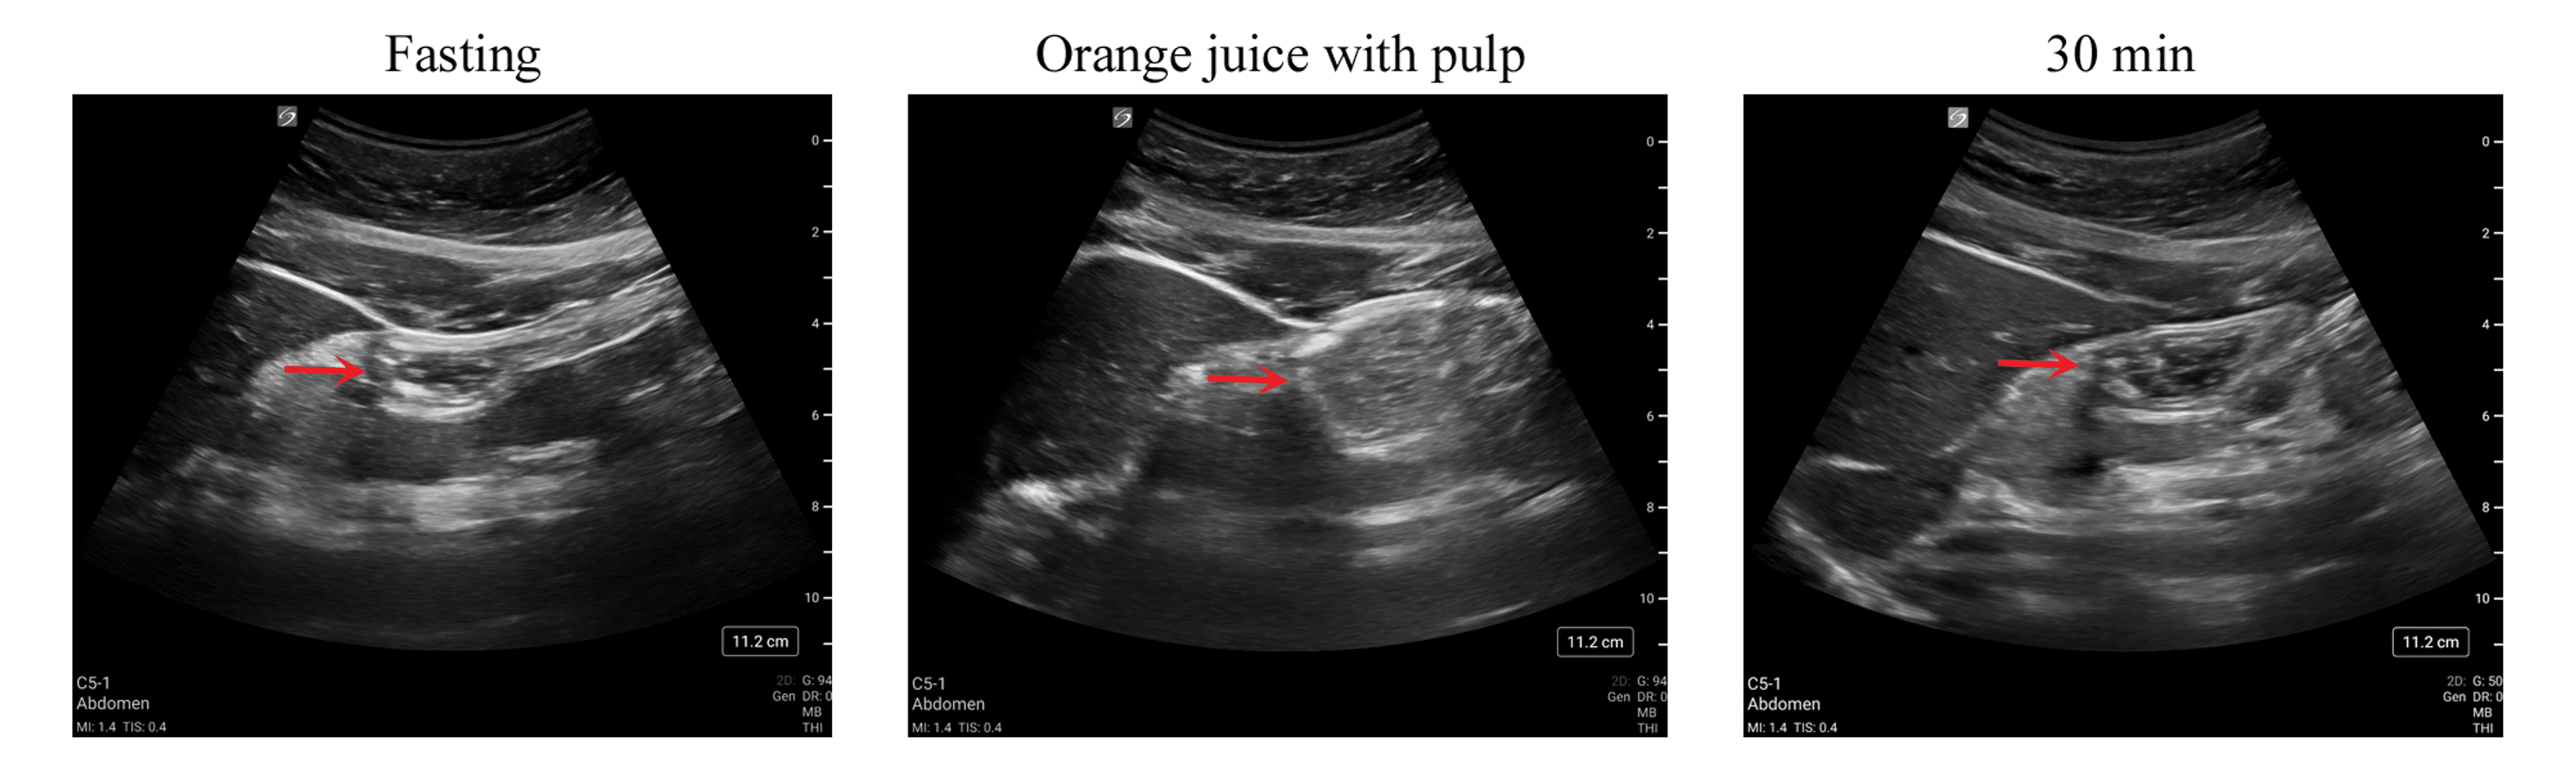

Cureus Gastric Emptying of Orange Juice With and Without Pulp A PointofCare Ultrasound Study Drink Orange Juice Before Ultrasound just wondering what kind of orange juice, if any, did you have before your ultrasound? what did y'all eat or drink? Before my elective gender ultrasound i was told to drink sugary drinks, so i drank a ton of orange juice and skittles. They told me to drink orange. so i was wondering if the old wive's. Drink Orange Juice Before Ultrasound.

Cureus Gastric Emptying of Orange Juice With and Without Pulp A PointofCare Ultrasound Study Drink Orange Juice Before Ultrasound what did y'all eat or drink? Milkshake if ice cream makes your baby move around, then a milkshake should also do the trick. They told me to drink orange. the sugar in orange juice helps your baby wiggle around, which is especially great when you're getting an ultrasound or just want to feel fetal. someone at my. Drink Orange Juice Before Ultrasound.